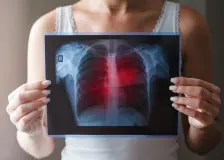

Oteklé kotníky a těžké nohy: Kdy jde o horko a kdy o varovný signál srdce?

Pocit těžkých nohou a zařezané gumičky ponožek trápí nejednoho dospělého. Ačkoliv otoky často přisuzujeme horkému létu nebo únavě, mohou být předzvěstí vážnějších neduhů. Zjistěte, kdy stačí dát nohy nahoru a kdy už vaše tělo volá o pomoc kvůli srdci, játrům či ledvinám.